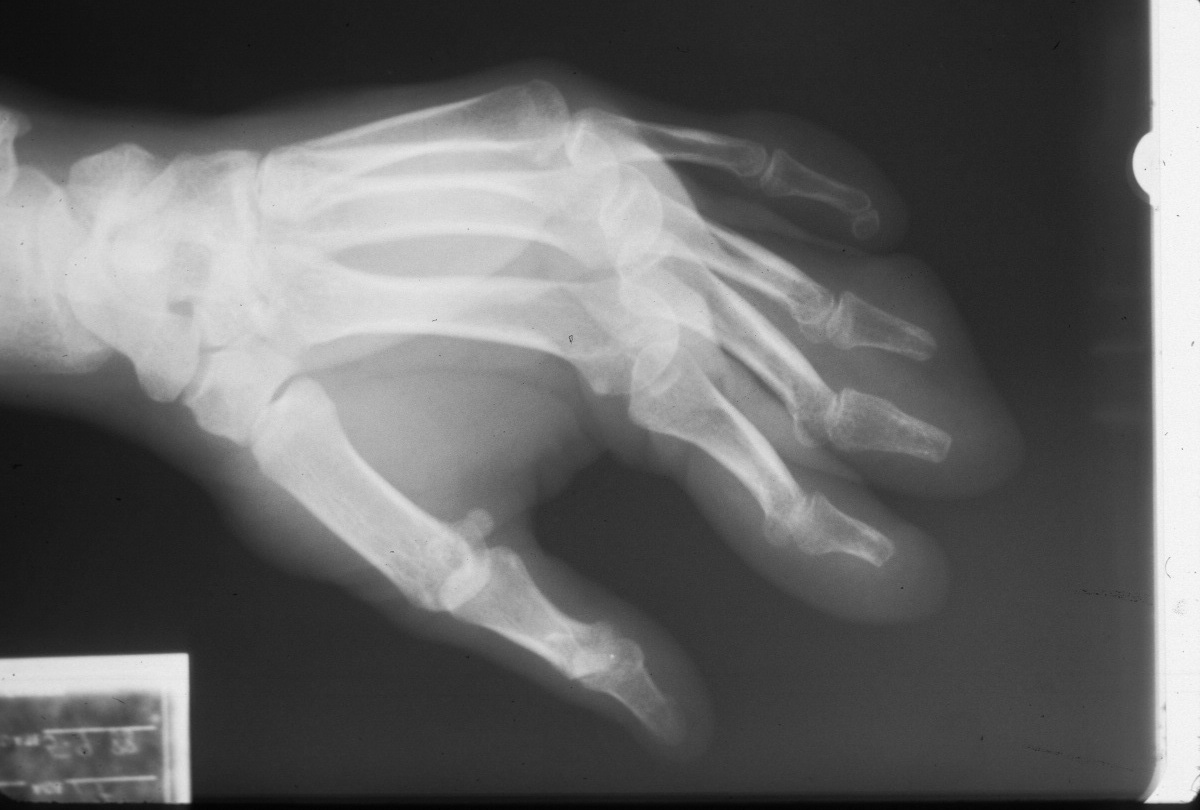

Initial injury:

Image Image Image